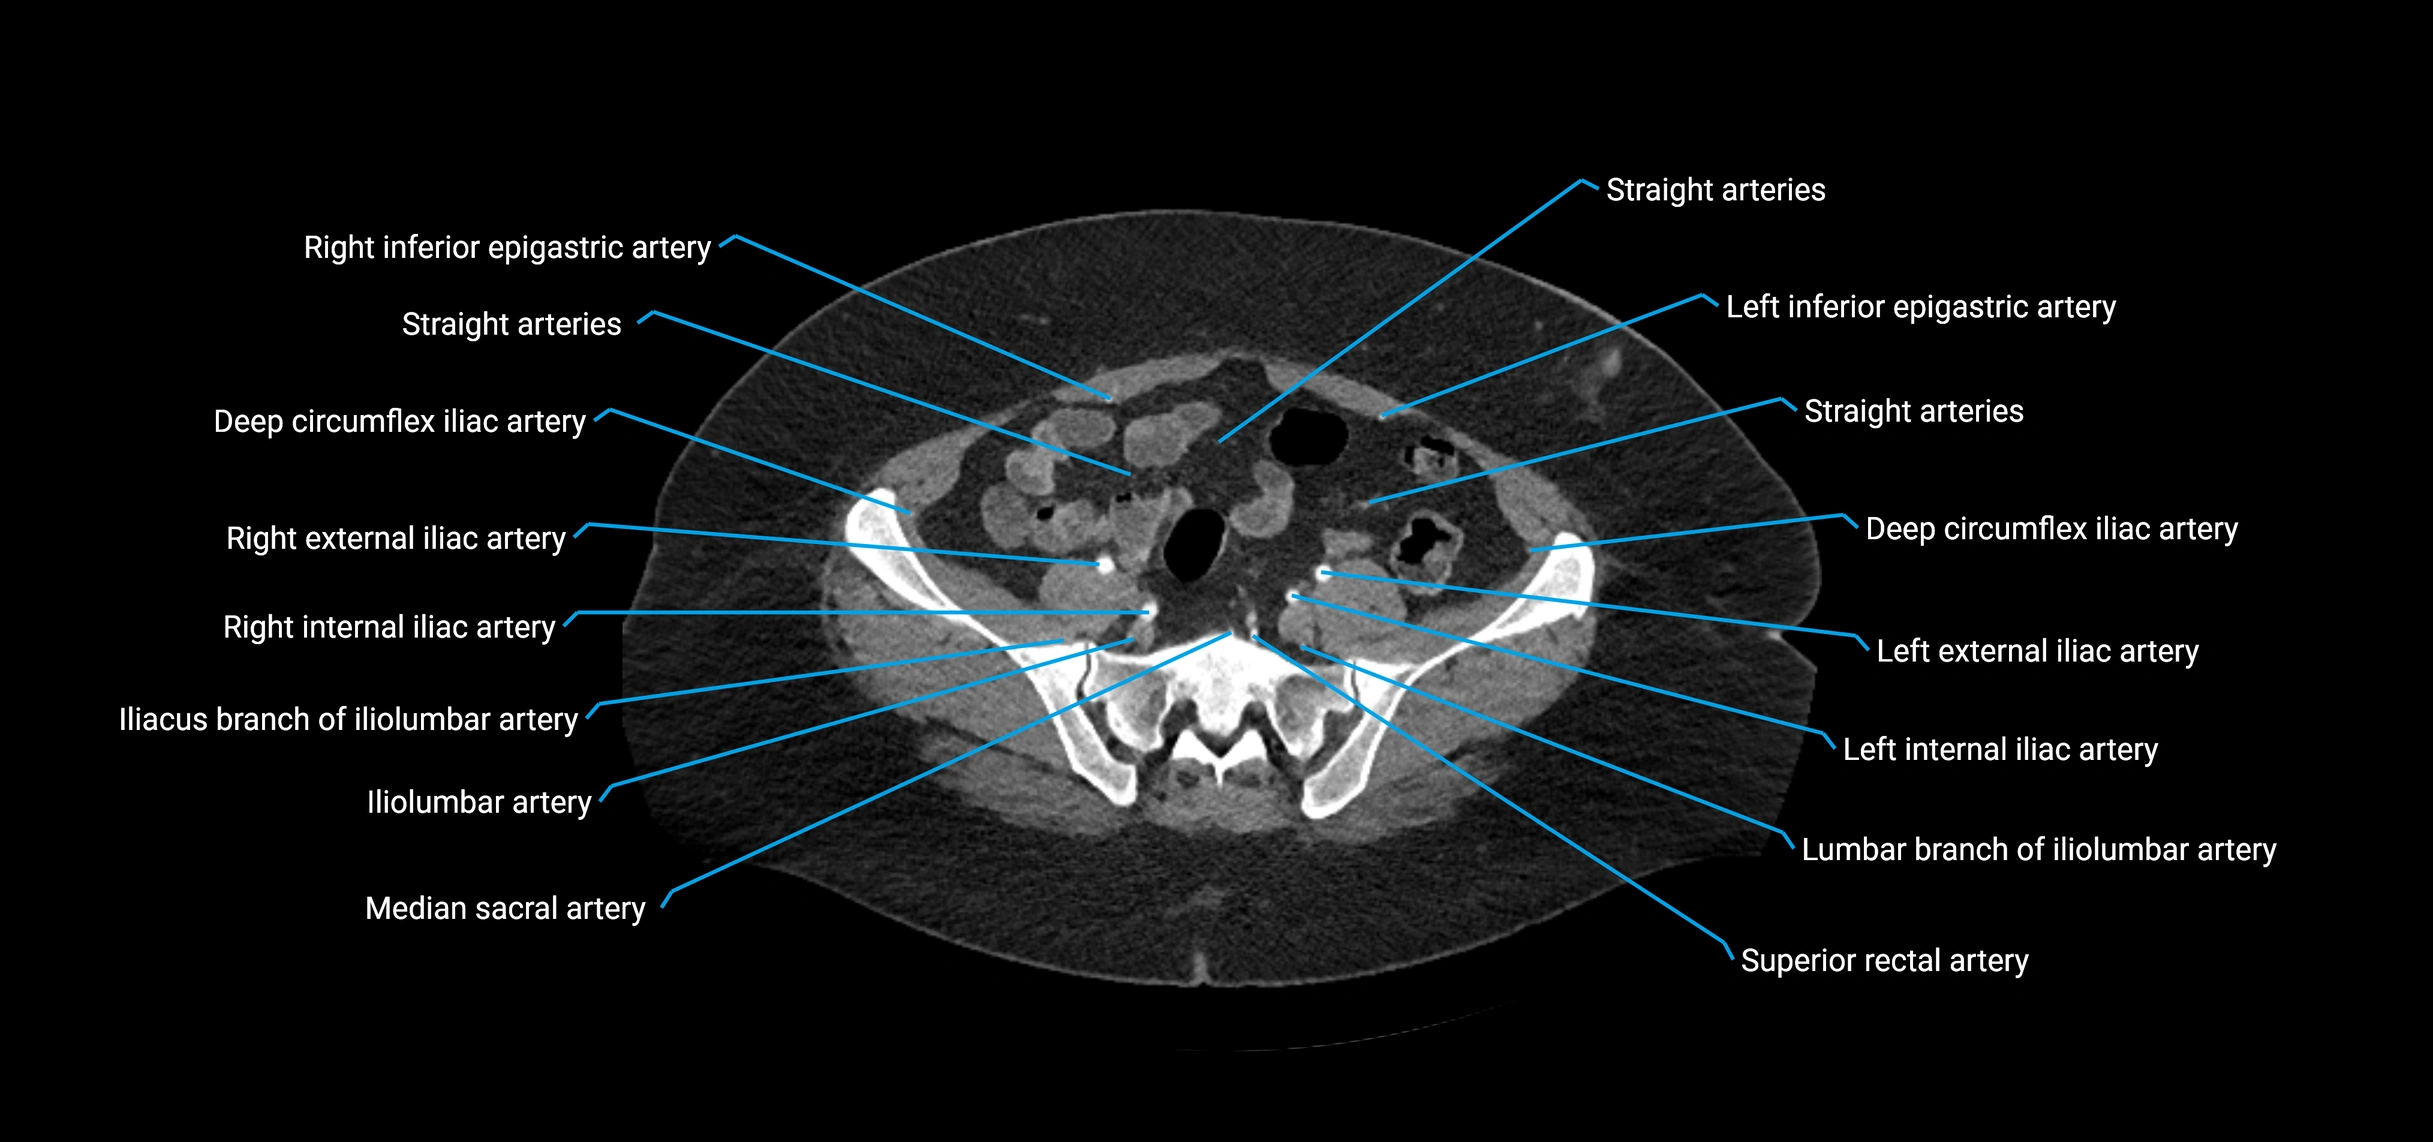

Contrast-enhanced CT (CTA):

• Gold standard for abdominal aortic imaging

• Provides excellent detail of lumen, wall, aneurysm, thrombus, and branch vessels

• Multiplanar and 3D reconstructions help in aneurysm measurement, stent graft planning, and dissection evaluation

• Detects acute rupture, traumatic injury, or occlusion with high sensitivity